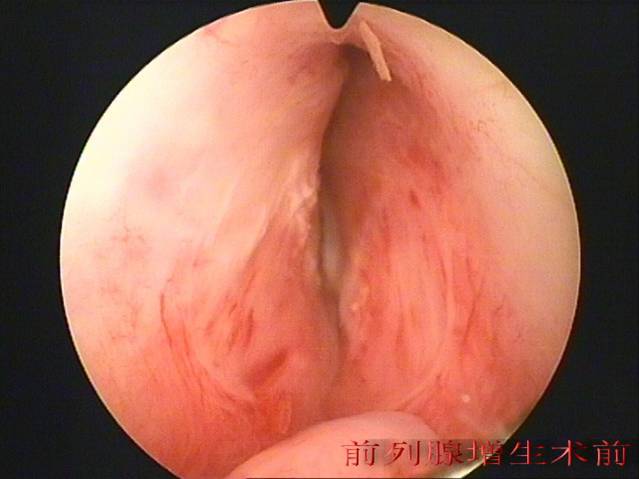

泌尿系统结石、前列腺增生症是我县常见病、多发病,2003年我院购进第一台进前列腺电切设备(德国产WOLF),由刘伟光副主任医师开展经尿道前列腺电切术、完成我院首例+前列腺增生微创手术,2009年泌尿外科成立之际在广州医学院微创中心袁坚主任指导下,先后开展经皮肾穿刺取石手术。科室先后派出多名医生到中山大学附属二院、广州医学院微创中心、中山市人医进修泌尿系结石微创治疗技术。自2010年医院再次投入科室购进进口输尿管镜、小儿输尿管镜、输尿管肾镜、经皮肾镜(德国的WOLF),全面开展肾、输尿管结石微创治疗手术,由于微创技术的开展,显著提高了泌尿系统结石、前列腺增生症手术治疗效果,获得了良好的社会效益。使科室处理泌尿系结石、前列腺疾病能力处于区域领先水平,科室近2年内逐步在该专业组开展泌尿系疾病腹腔镜治疗手术,成功开展腹腔镜下肾切除术、肾囊肿去顶、精索静脉曲张高位结扎手术,新技术的应用不仅使该专业组成为科室优势专业,也为我县常见病、多发病的有效治疗做出了贡献。

前列腺微创术前后